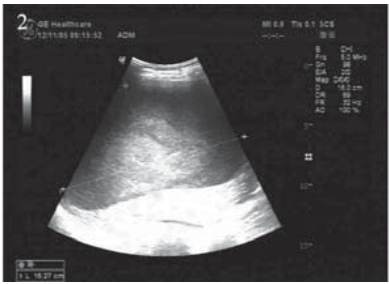

患者,女,66岁。2011年12月因“进食哽噎3 月余”就诊,查胃镜:贲门大弯后壁可见一大小约 3.5 cm×3.9 cm的不规则溃疡,周边堤样隆起。全 身CT等检查提示无其他部位转移,遂于2011年12 月22日在上海中山医院行贲门癌根治术,术中探 查见贲门部病灶,约3 cm×4 cm,质地中等,周围 脏器未见异常,遂行贲门癌根治术,食管胃机械 吻合。术后病理:“贲门”溃疡型腺癌,Ⅱ~Ⅲ级, 侵及胃壁全层及周围脂肪组织,淋巴结(3/20) 见癌转移。TNM分期为:ⅢB期(T4aN2M0), 术后复查CT:两肺少许间质性改变,后腹膜淋巴 结稍大,右肾上极局部形态异常,伴右肾囊肿。 2012年1月27日起予“奥沙利铂+替吉奥”化疗六周 期,期间复查CT无转移依据。2012年8月再次复 查CT:左肺叶间胸膜增厚,右肺上叶可疑小结 节,胃癌术后改变,肝脏小囊肿可能,肝右叶包 膜下包裹性积液,右肾上极梗死后遗改变可能, 右肾小囊肿、小结石,腹盆腔积液,见图 1。查 CA199:154.71 IU/ml,CEA:15.65 ng/ml,肿瘤 进展,遂予“紫杉醇+替吉奥”化疗一周期。2012 年11月初患者出现右上腹胀痛,进食后明显,伴 恶心、呕吐,呕吐物为胃内容物。遂入住我科。 入院查体:右上腹可触及包块,有压痛,中上腹 部可见陈旧性手术疤痕,肝区叩痛明显,余未 见异常。血常规、肝肾功能正常。CA199:143.3 IU/ml,CEA:16.56 ng/ml。腹腔B型超声:腹腔 积液,最大前后径约26 mm;肝包膜下巨大囊性 占位,大小约16.3 cm×9.5 cm,见图 2 。胸部CT未 见异常。腹盆部CT:胃癌术后改变,肝脏小囊肿 可能,肝右叶包膜下包裹性积液较前明显增加, 右肾上极梗死后遗改变可能,右肾小囊肿、小结 石,右肾轻度积水,腹盆腔积液,见图 3。

图 2 肝包膜下巨大囊性转移瘤患者腹部B型超声 Figure 2 Abdominal US of huge cystic metastatic tumor of hepatic subcapsular The huge cystic mass under the liver capsule,the maximum anteroposterior diameter is 16.3cm×9.5cm |